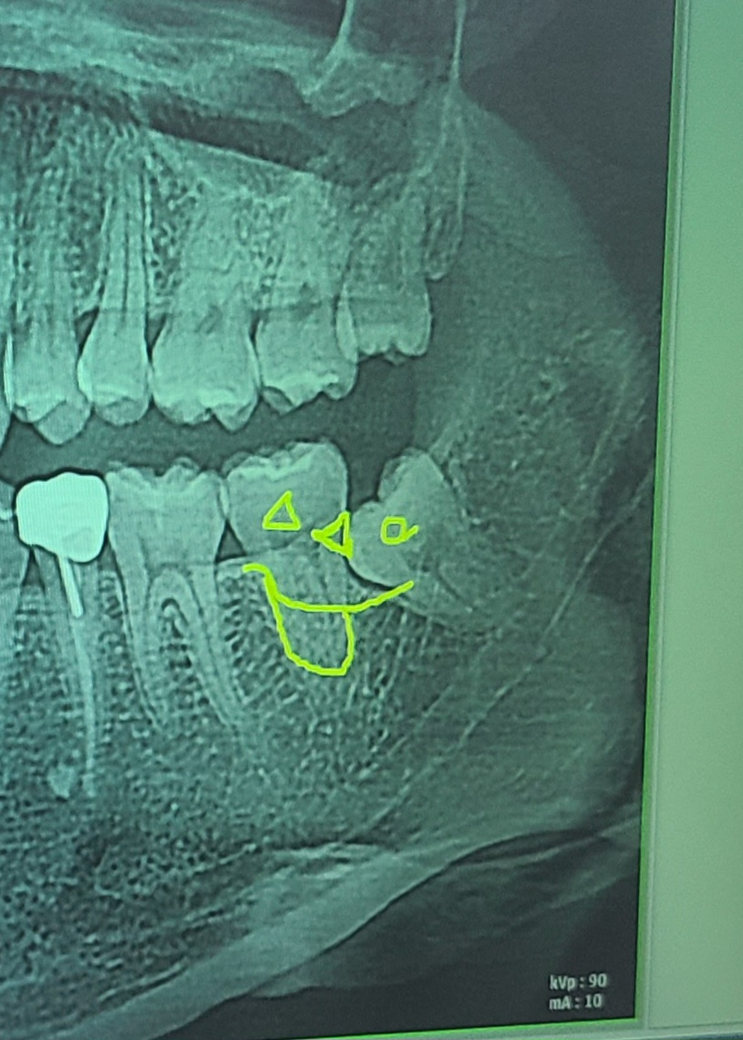

이 사랑니는 뽑아야 되나요? (사진첨부)

(왼쪽 사랑니 위아래 사진)

어제 오른쪽 사랑니가 아파서 발치한 후에 왼쪽 사랑니 위아래도 발치해야겠다고 의사선생님께서 말씀하셨습니다

해당부위의 사랑니는 아직 잇몸위로 맹출되지 않았고 앞의 치아에 영향을 미치지 않고 있기 때문에 발치를 하지 않아도 크게 문제가 되지 않습니다.

나중에 부분적으로 맹출이 되거나 앞의 치아에 영향을 미치는 소인이 보인다면 발치를 해주는것이 좋습니다.

사랑니는 웬만하면 뽑으시는 것이 좋으며 사진상의 사랑니도 발치를 해야하는 사랑니입니다.

불편하시다면 발치를 하시는게 좋지만, 잇몸뼈 안쪽에 잇어서 크게 문제가 되거나 하지는 않을꺼 같긴합니다.

현재 사랑니 방향이 누워 있기에 방치하는 경우 바로앞의 어금니를 상하게 할 가능성이 높기에 빠른시일내에 발치가 필요로 됩니다.

현재 왼쪽 아래 어금니는 뼈에 매복되어 있는 상태이고 두번째 큰 어금니(37번)에 영향을 주고 있는 상태이긴 합니다.

뽑는 과정이 쉽지는 않을 것 같습니다. 일단, 잇몸을 절개하고 사랑니 주변 뼈를 조금 갈아낸 뒤 사랑니를 뽑게 되는데 사랑니 뿌리 끝 부분이 조금 남게 될 수도 있습니다.

현재 나이가 20대 극초반이라면 해당 사랑니가 좀 더 맹출할 가능성도 있지만 옆에 치아에 걸려있는 상황(locking)이기 때문에 더이상 나오지 않을 가능성도 있습니다.

사랑니가 옆에 두번째 큰 어금니에 영향을 줘서 치근흡수(뿌리흡수)나 충치의 가능성도 있습니다.